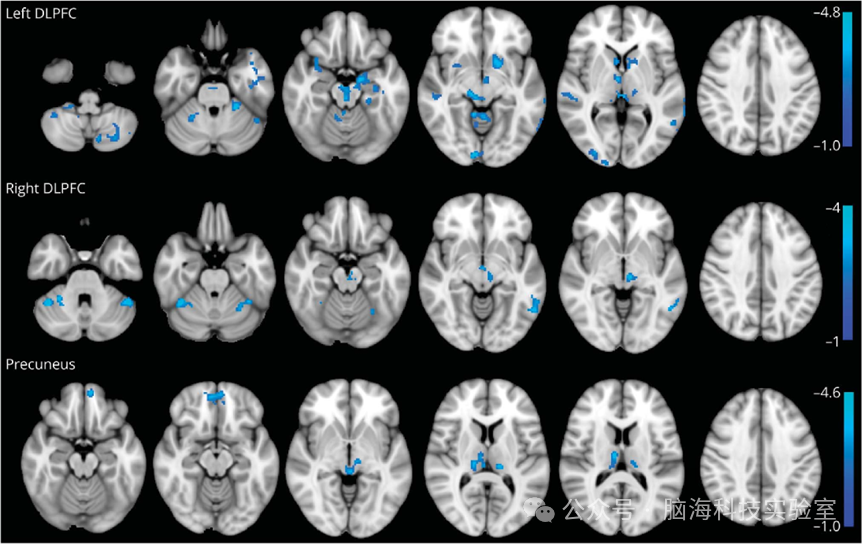

根据双重综合征假说,患有视觉空间障碍的帕金森病(PD)患者比主要表现为执行功能障碍综合征的患者更有可能进展为痴呆。研究的目标是调查在认知功能正常的初诊帕金森病患者中,背外侧前额叶皮层(DLPFC)和楔前叶(PCun的早期功能连接变化是否能够识别出不同的认知表型。DLPFCPCun分别对前额叶执行功能和视觉空间功能至关重要。

研究从意大利的运动障碍诊所连续纳入了临床发病时间不超过2年的新诊断、未经药物治疗的帕金森病患者,其蒙特利尔认知评估量表(MoCA)评分正常。同时,在非血缘关系的患者亲属中纳入了性别和年龄匹配的健康对照组(HCs)。参与者在基线(T0)时接受了3T-fMRI检查,以基于种子点的方法研究DLPFCPCun的静息态功能连接(rs-FC)。研究对帕金森病患者的rs-FC值的z分数进行了K均值聚类分析,以识别具有共同连接模式的患者群体。在T03.5年随访(T1)时,研究评估了不同帕金森病聚类群体之间的神经生理学、运动和非运动量表的差异。

该研究在T0时纳入了68名帕金森病患者(27%为女性;平均年龄60±9岁;Hoehn & Yahr评分1.4±0.5MoCA评分27.9±1.6)和31名健康对照组(39%为女性;平均年龄64.2±9.3岁)。42名患者完成了T1的评估。与健康对照组相比,患者在多个皮层和皮层下区域的DLPFCPCunrs-FC均降低。聚类1在所有研究的兴趣区域的rs-FC值均较低,而聚类23rs-FC值分别较高和中等。尽管在T0时没有任何患者符合轻度认知障碍(MCI)的标准,但聚类1的患者年龄更大,在整体认知、前额叶执行功能和记忆领域的表现均低于聚类23(所有p<0.031)。T1时,与聚类2相比,聚类13在整体认知、前额叶执行功能和视觉空间领域的恶化更为明显,并且非运动和运动症状也更为严重(所有p<0.04),且聚类13MCI的发生更为频繁。

在没有轻度认知障碍的初诊帕金森病患者中,DLPFCPCun的早期功能连接变化确实存在,并且可以区分不同的认知表型,这一点在纵向临床观察中得到了证实。

1帕金森病患者和健康对照组在所选ROI中静息状态功能连接的群体差异图